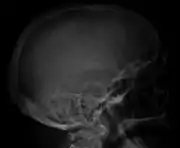

The diagnostic examination of a person with suspected multiple myeloma typically includes a skeletal survey. This is a series of X-rays of the skull, axial skeleton, and proximal long bones. Myeloma activity sometimes appears as "lytic lesions" (with local disappearance of normal bone due to resorption). And on the skull X-ray as "punched-out lesions" (raindrop skull). Lesions may also be sclerotic, which is seen as radiodense.[52] Overall, the radiodensity of myeloma is between −30 and 120 Hounsfield units (HU).[53] Magnetic resonance imaging is more sensitive than simple X-rays in the detection of lytic lesions, and may supersede a skeletal survey, especially when vertebral disease is suspected. Occasionally, a CT scan is performed to measure the size of soft-tissue plasmacytomas. Bone scans are typically not of any additional value in the workup of people with myeloma (no new bone formation; lytic lesions not well visualized on bone scan).

Skull X-ray showing multiple lucencies due to multiple myeloma